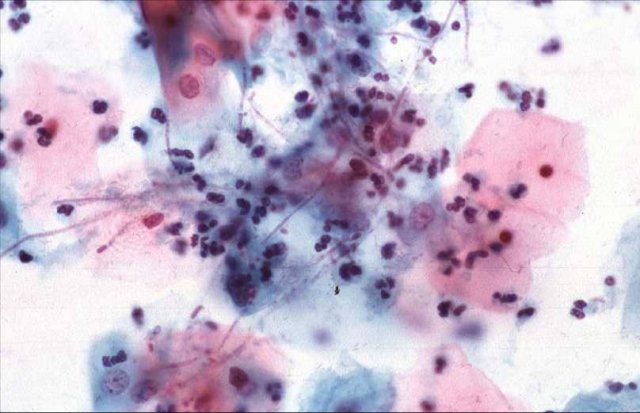

Кольпит — это заболевание, при котором происходит активизация воспалительного процесса некоторых женских органов, но в основном поражается слизистая оболочка влагалища. Другое название этой проблемы — вагинит. Запущенное заболевание может привести к расширению воспаления, которые переходит не только на вульву, но и на наружные половые органы. Такое более «расширенное» воспаление носит название вульвовагинит.

Бактериальный (или специфический) кольпит — воспаление, вызванное полностью патогенной микрофлорой, делится на разновидности по типу микроорганизмов. Патогенные микроорганизмы проникают во влагалище при разных обстоятельствах, например, во время полового акта, с белья или даже в результате медицинского вмешательства.

Кольпит, вызванный условно-патогенными микроорганизмами, называется неспецифическим бактериальным кольпитом. Условно-патогенные бактерии вызывают воспаление только при определенных условиях. Такие бактерии присутствуют в организме всегда, при этом выполняя определенные функции. В результате ослабления иммунитета, стресса, приёма лекарств, в том числе антибиотиков, устойчивость организма снижается и такие бактерии, чрезмерно размножаясь, нарушают микрофлору влагалища и вызывают воспалительный процесс.